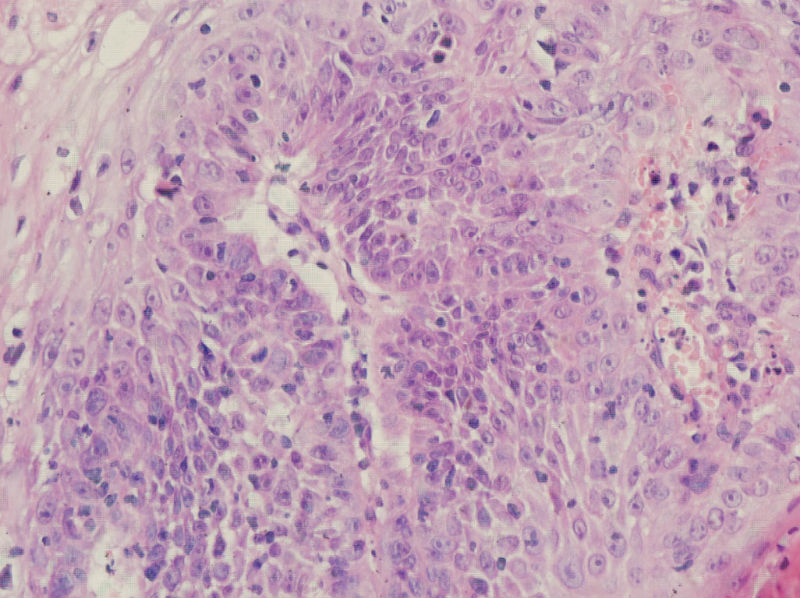

男,45岁,上唇菜花样肿物,请老师指教

图2

高分化鳞癌

倾向于鳞癌,恶黑不除外。